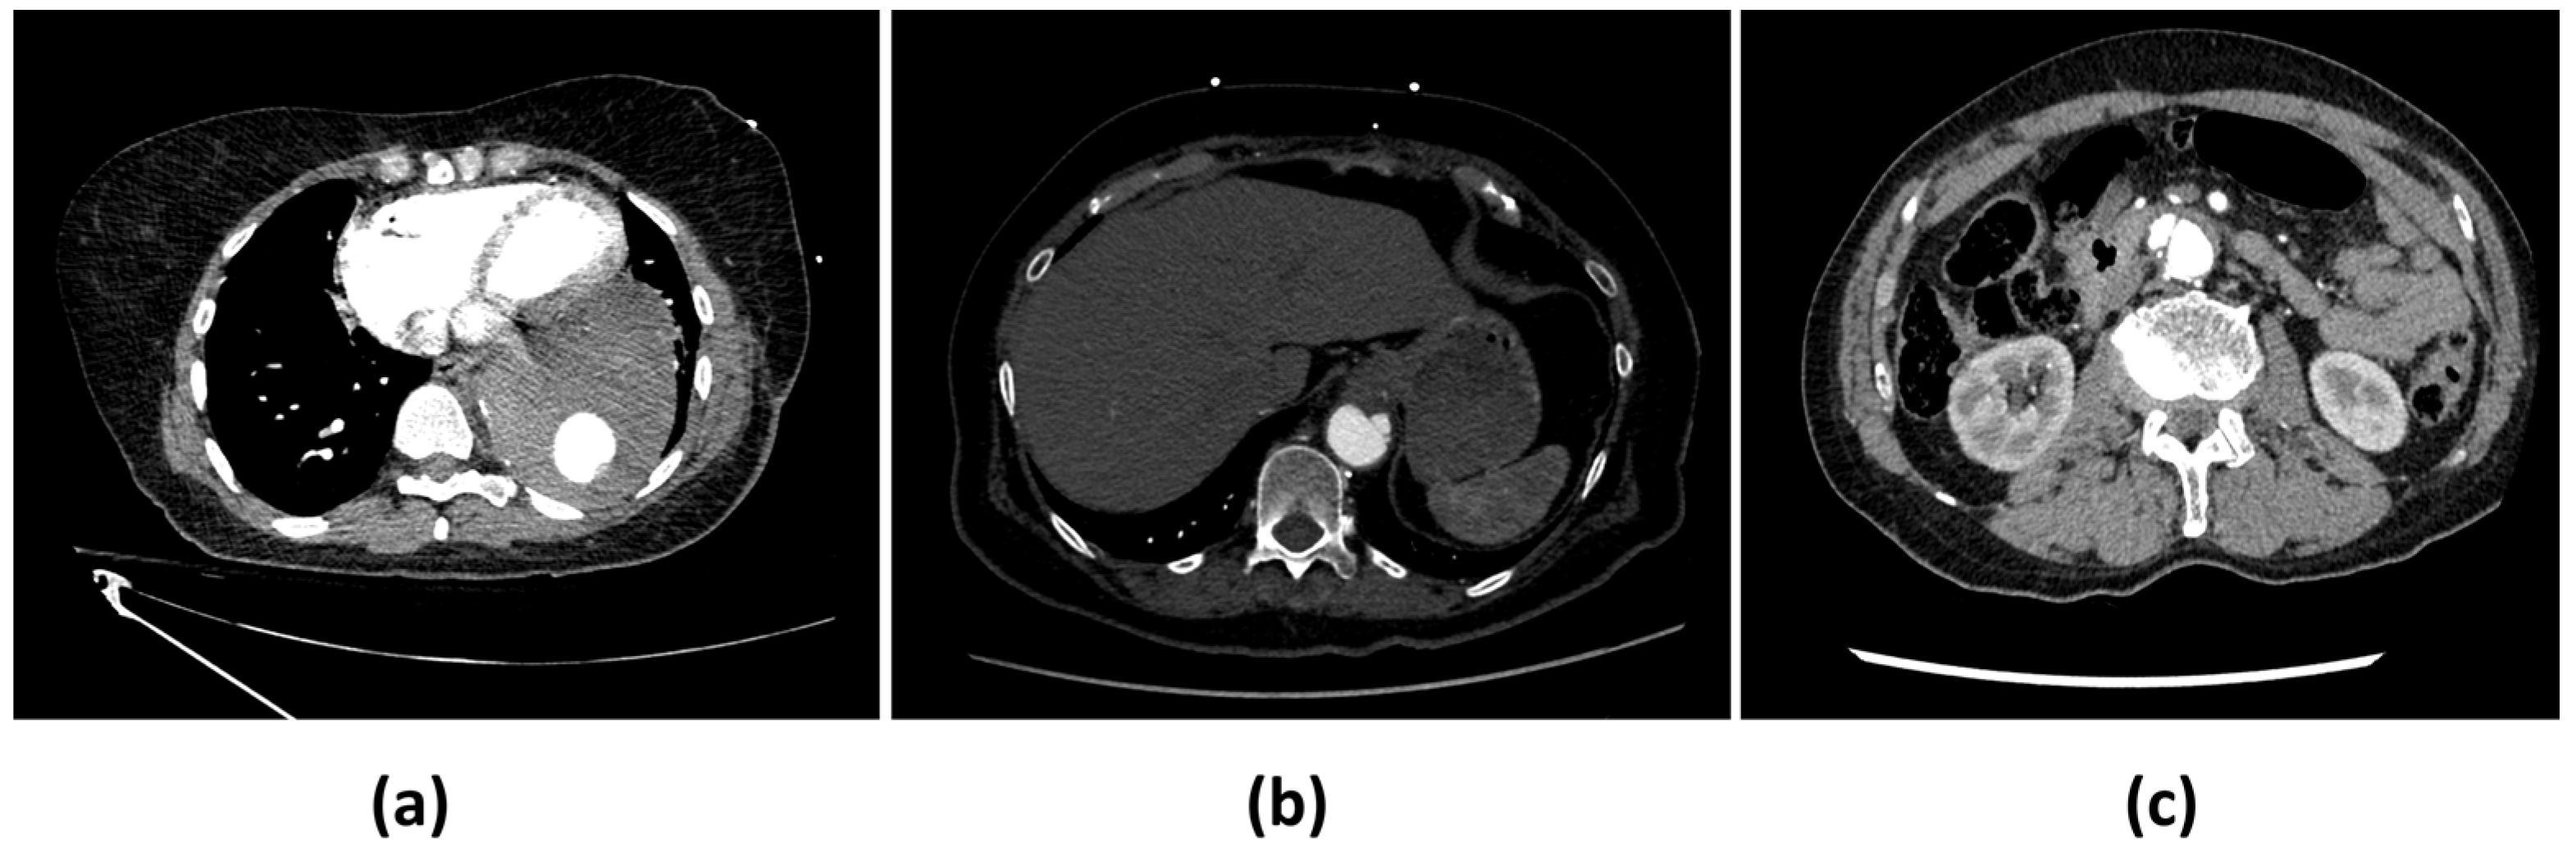

| Main Reasons for False Negatives (n = 8) | Main Reasons for False Positives (n = 32) |

|---|---|

| Intramural hematoma (IMH) (4) | Inadequate contrast opacification (13) |

| Penetrating atherosclerotic ulcer (PAU) (2) | Motion artefacts (10) |

| Acquisition artefacts (2) | Instances of pathology mimicking dissection (7) |

| Interference from stent grafts (2) |